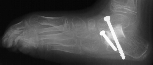

Postoperative X-rays:

- Left Talocalcaneal angle is 24 degrees, Talonavicular angle is 2 degrees

- Right Talocalcaneal angle is 28 degrees, Talonavicular angle is 2 degrees